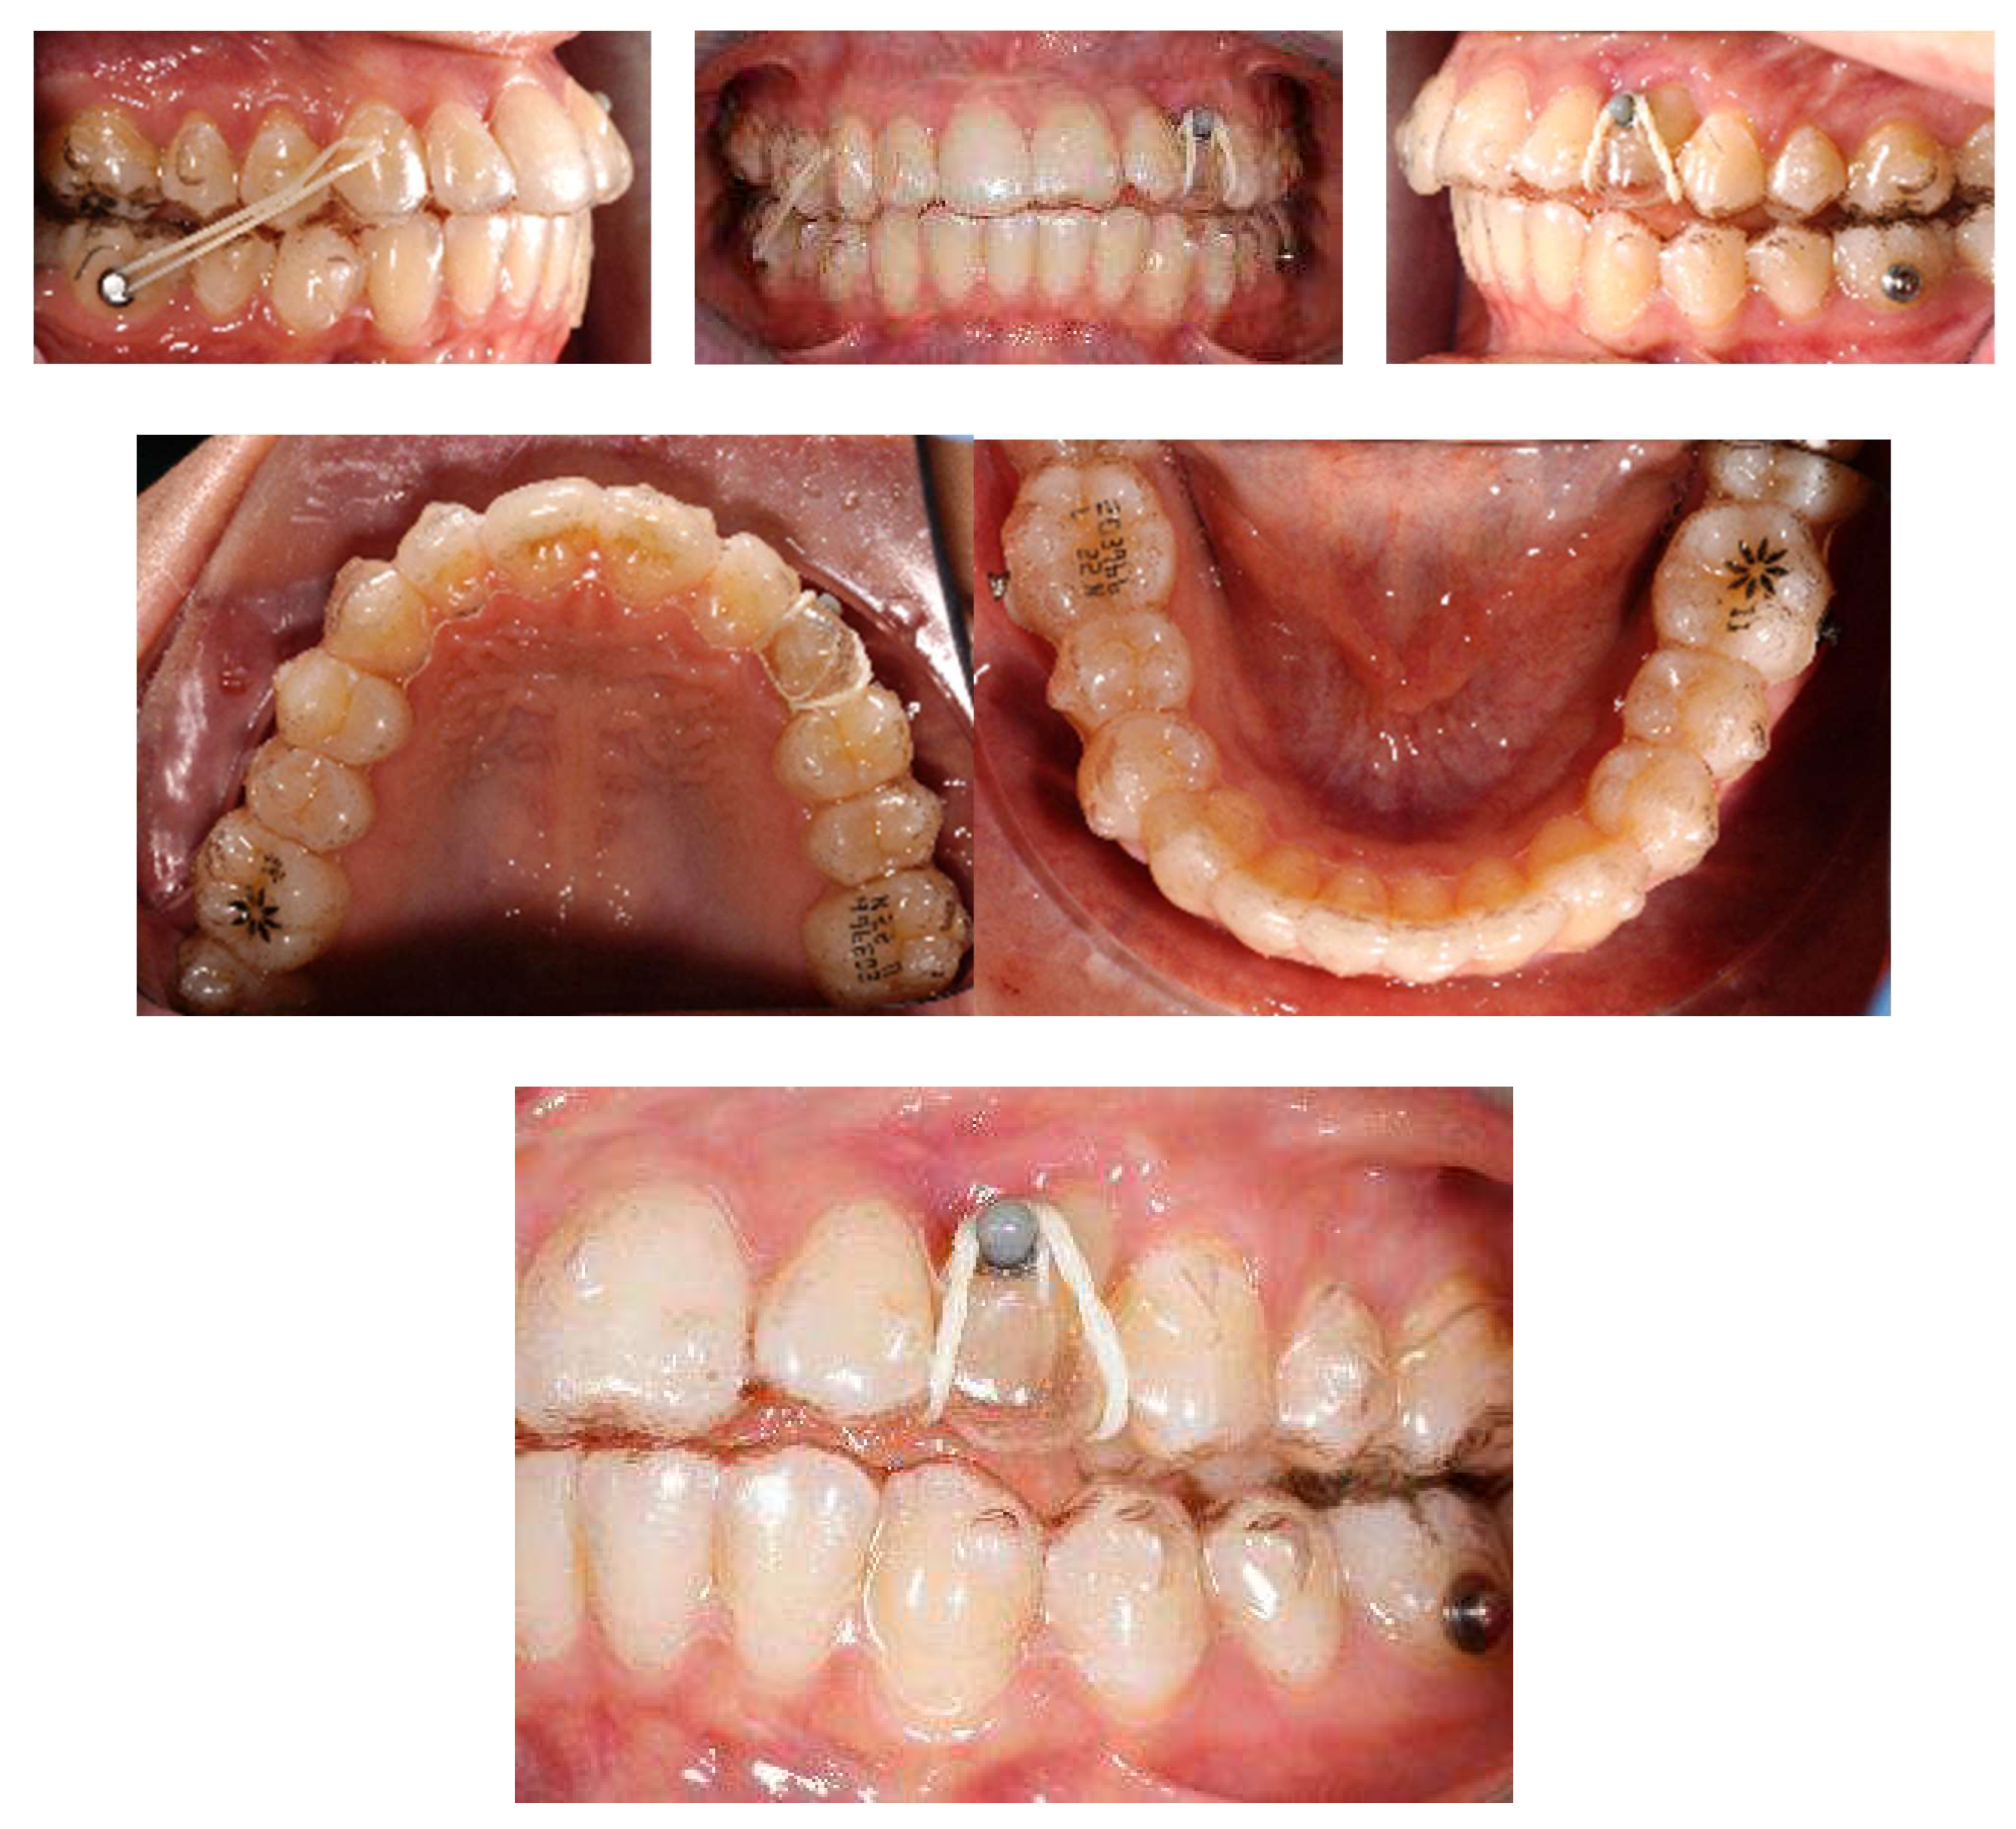

This was followed by the insertion of a TAD (3M Unitek 8 mm × 1.5 mm) on the buccal side between the upper second premolar and first molar on the buccal side. Thereafter, a TMA 0.018 × 0.025-in cantilever spring was modelled and applied directly to the TAD and activated in extrusion and distalisation, applying a force of 50 g to achieve the movement of the canine crown from lateral incisor apex (Figure 13).

Figure 13.

After the surgical exposure of the impacted canine, a TAD was inserted between 1.5 and 1.6 and a 0.017 × 0.025 TMA was tied to the wire chain.